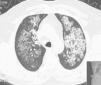

Pulmonary Alveolar Proteinosis (PAP) is a rare diffuse lung disease with three clinical forms, congenital, acquired (idiopathic) and secondary, characterized by an accumulation of large amounts of a phospholipoproteinaceous material in the alveoli due to a deficiency in granulocyte-macrophage colony-stimulating factor (GM-CSF) activity1–14 (Fig. 1). This is associated with an abnormal macrophage function and an impaired clearance of surfactant from the lungs. PAP has a prevalence of 3.7 cases per million, a male preponderance (4:1 male/female ratio) and 80% of the cases are reported during the third and fourth decade of life.6

The first patient was male, 39 years old, smoker, baker, diagnosed with PAP one month before the first WLL, based on clinical, radiological and BAL features and the presence of serum GM-CSF antibodies. At disease presentation he had respiratory insufficiency associated with an extensive bilateral lung involvement observed in HRCT-scan and a bilateral WLL was performed with 9.2 and 11.8L of saline solution instilled into the right and left lung respectively. After a short period of clinical, functional and radiological improvement, the patient's condition worsened with the spread of the radiological lung opacities and respiratory insufficiency. This clinical deterioration coincided with his return to the workplace. In fact, bakery flour had been described as a potential trigger.16 A second bilateral WLL was performed three months later, and 15.3 and 10.7L of saline solution were then instilled. After this procedure and cessation of his previous work environment, the patient maintained clinical stability.

The second patient submitted to WLL was a female, 47 years old, farmer, non-smoker, no comorbidities, with the diagnosis of PAP one month before the first WLL based on clinical, radiological and BAL features and the presence of serum GM-CSF antibodies. The clinical presentation was very similar to the first patient's, with dyspnea on exertion and a dry cough associated with respiratory insufficiency and wide bilateral crazy paving pattern opacities in the HRCT scan. After the diagnosis, a WLL was performed with instillation of 14 and 10.8L of saline into the right and left lung respectively. After a brief initial clinical improvement, she was submitted to another WLL 1.5 months later, since she had become more symptomatic and with paO2<60mmHg. With this procedure, a total of 13.5 and 10.6L were instilled into the right and left lung respectively. Four months later a third WLL was performed because of clinical deterioration and at this time 15.5 and 11.1L were instilled into right and left lung respectively (Fig. 4). After this procedure, the patient achieved clinical, functional and radiological stability.

The third patient included was a male, 45 years old, ex-smoker, tire factory worker, with the diagnosis of PAP during a nocardia-induced cerebral abscess evaluation and treatment. As with the other two patients, the diagnosis was established by radiological and BAL typical features associated with serum GM-CSF antibodies. However, he had had a previous thoracic HRCT scan with bilateral crazy paving pattern two years earlier. One year after the diagnosis, he became more symptomatic, with dyspnea on exertion and respiratory insufficiency (paO2-57mmHg) and therefore was submitted to a WLL with instillation of 15.5 and 15.3 of saline into right and left lung respectively. After this procedure, he achieved significant clinical, functional and radiological improvement.